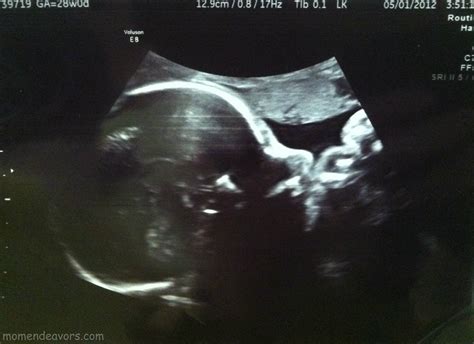

Prenatal care is a crucial aspect of ensuring the health and well-being of both the mother and the developing baby. Among the various prenatal tests and screenings, 28 Weeks Sonography stands out as a pivotal milestone. This ultrasound examination, typically performed around the 28th week of pregnancy, provides valuable insights into the baby's development and the mother's health. Understanding the significance of this procedure can help expectant parents prepare for what to expect and how to interpret the results.

28 Weeks Sonography is a routine ultrasound scan conducted during the third trimester of pregnancy. This scan is often referred to as the "anomaly scan" or "mid-pregnancy scan" and is usually performed between 26 and 28 weeks of gestation. The primary goal of this ultrasound is to assess the baby's growth, development, and overall health. It also helps in identifying any potential complications that may require further monitoring or intervention.

During a 28 Weeks Sonography scan, the expectant mother will lie on an examination table with her abdomen exposed. A gel is applied to the abdomen to enhance the transmission of ultrasound waves. A transducer, a handheld device, is then moved over the abdomen to capture images of the baby. The procedure is painless and non-invasive, typically lasting between 20 to 30 minutes.

The ultrasound technician will measure various parameters, including:

• The baby's head circumference

• The baby's abdominal circumference

• The length of the baby's femur (thighbone)

• The amount of amniotic fluid

• The position of the placenta

These measurements help in estimating the baby's weight and assessing overall growth. The technician will also check for any structural abnormalities in the baby's organs, such as the heart, brain, kidneys, and spine.